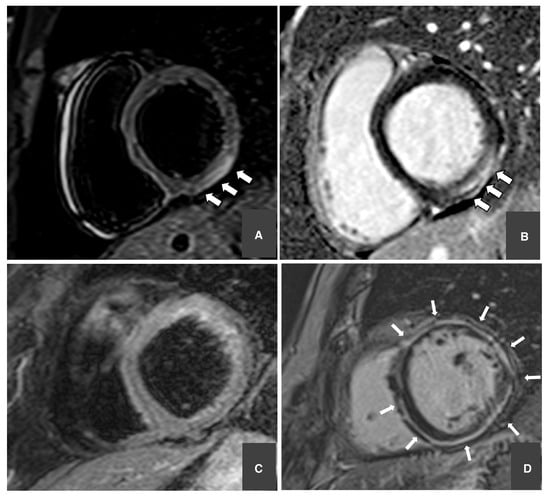

2. Acute Coronary Syndromes

3. Acute Myocarditis

4. Takotsubo Syndrome